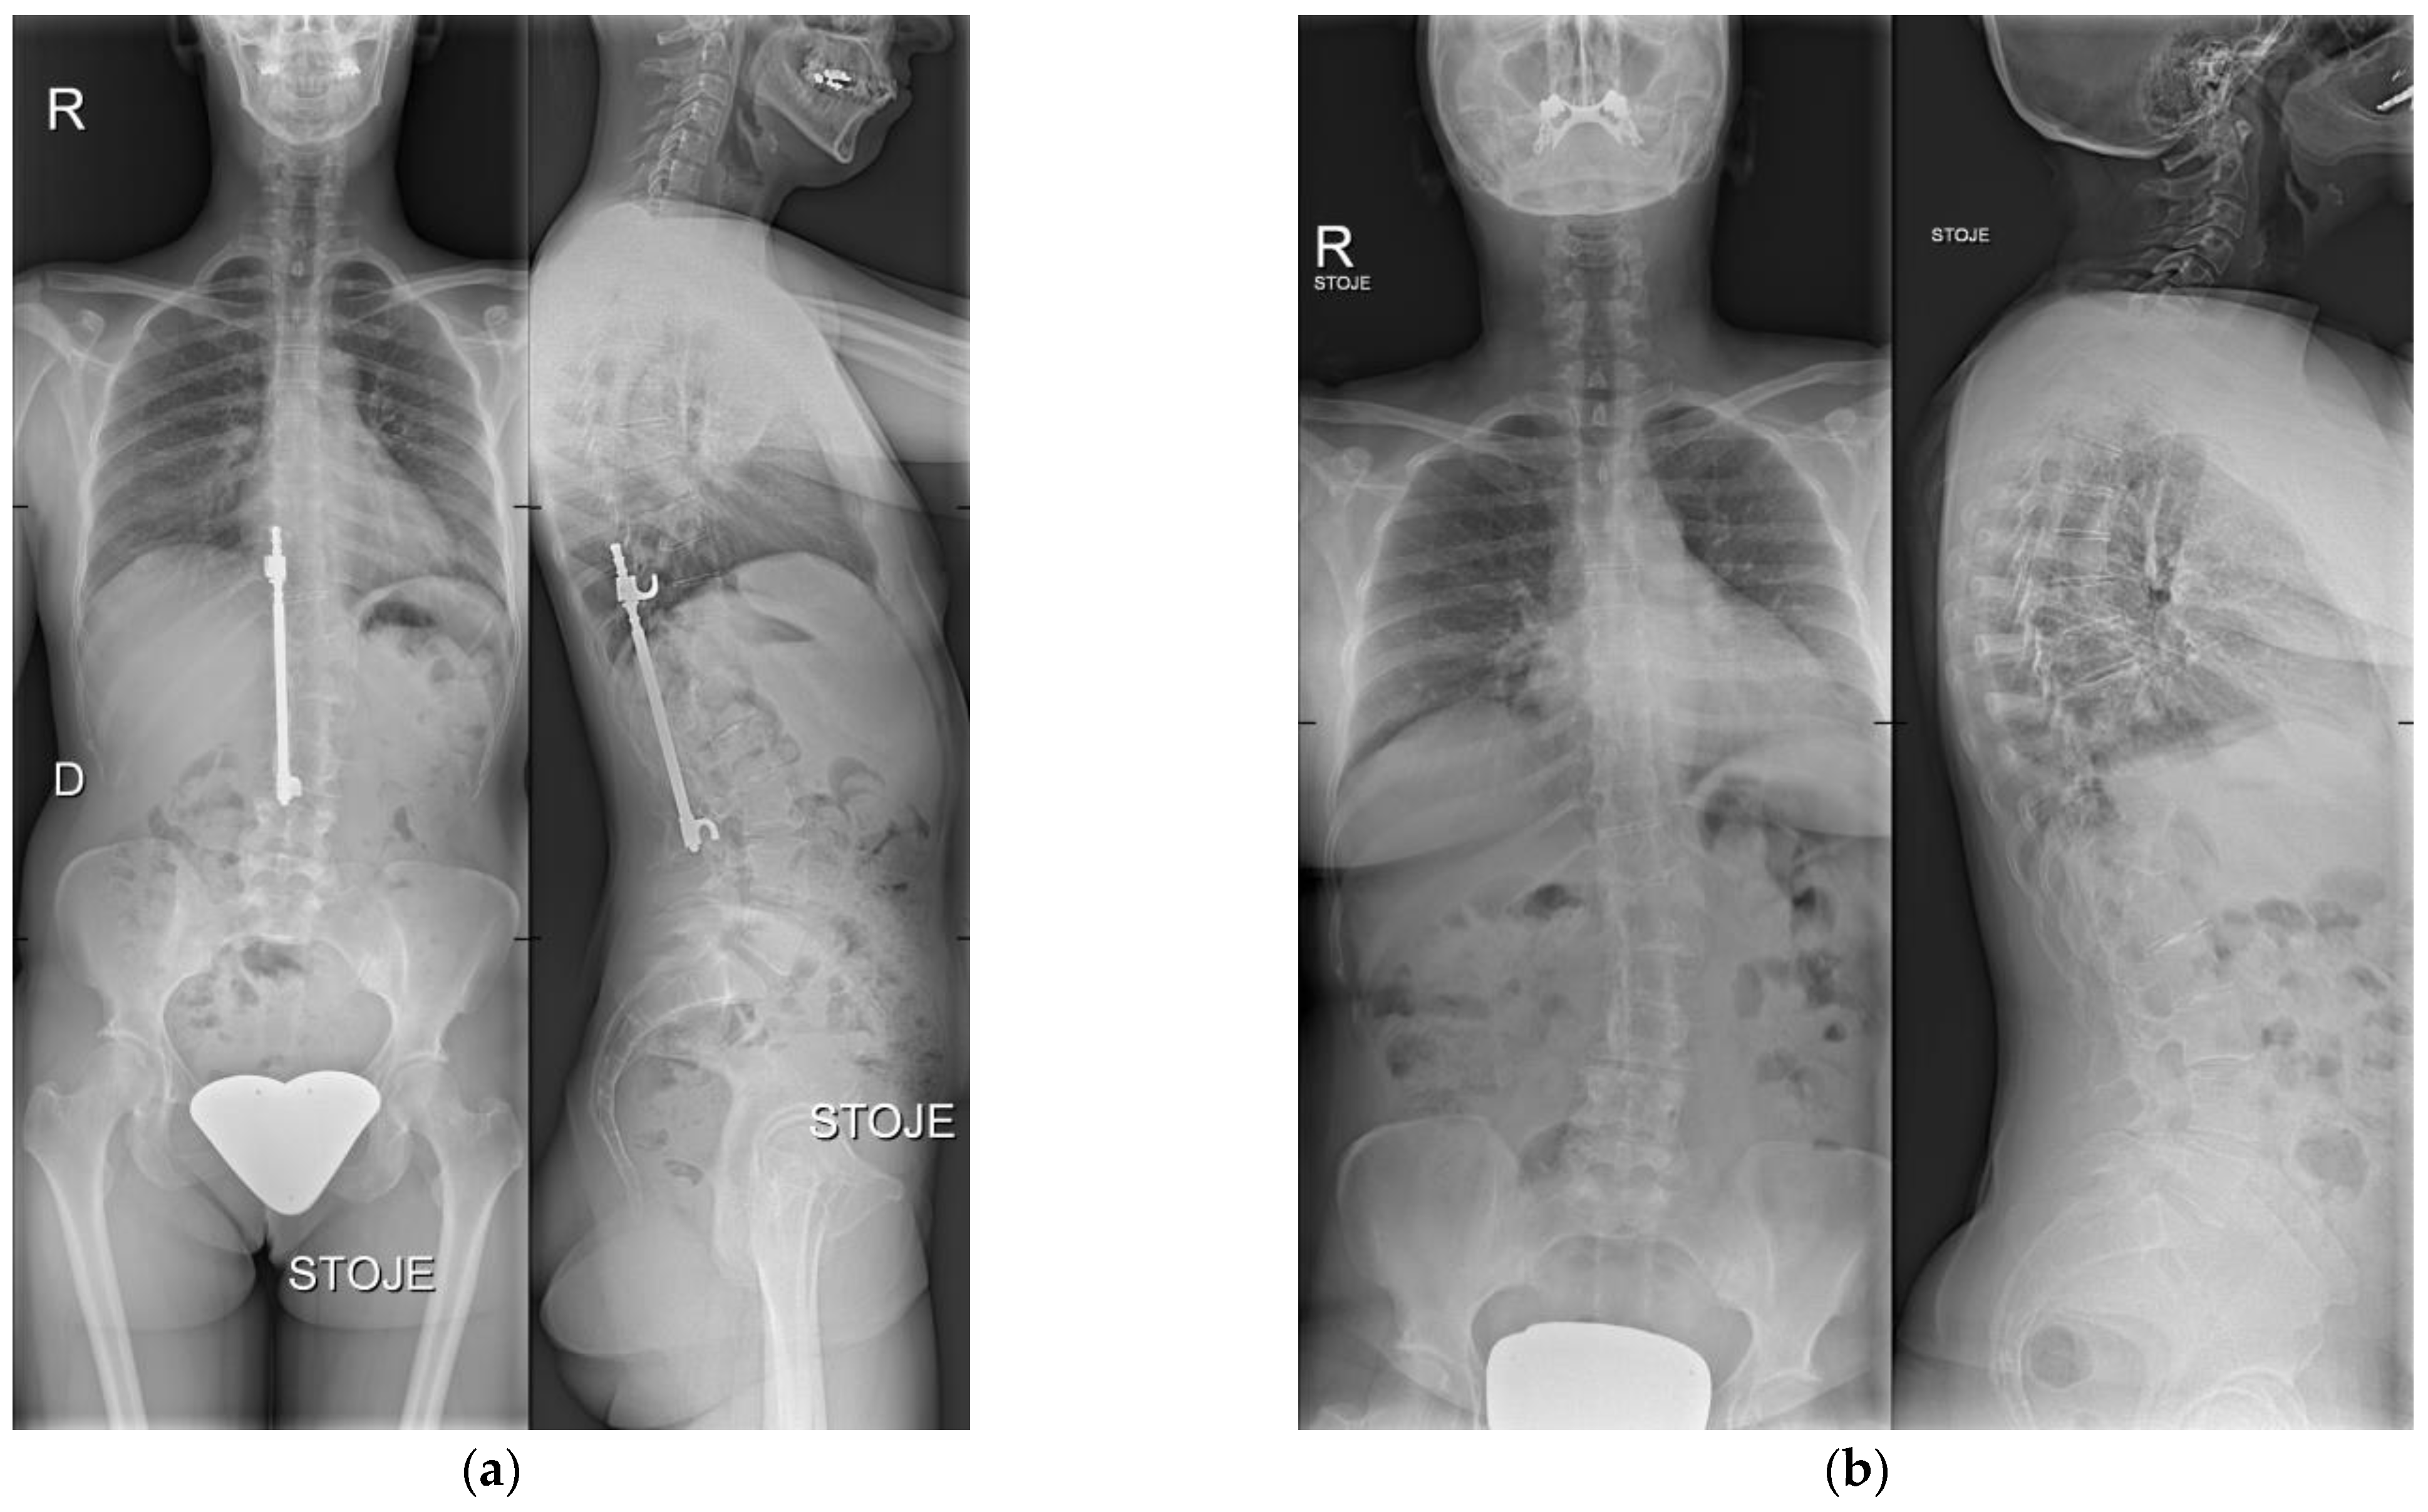

We performed a retrospective, institutional review board-approved (No. 2/2022) analysis of a single-institution case series of 12 consecutive patients with adolescent idiopathic scoliosis, treated primarily with surgical correction using HR instrumentation (Figure 1a) between 1982 and 1997, and afterward with watchful waiting of residual spinal deformity after HR instrumentation removal (Figure 1b), whereby no patient consented to surgical residual deformity correction. Written informed consent from the patients was obtained.

Figure 1.

(a) X-ray taken before HR instrumentation removal. Anteroposterior (left) and lateral (right) view. (b) Most recent X-ray after HR instrumentation removal. Anteroposterior (left) and lateral (right) view.

This study aimed to assess long-term radiological outcomes in patients from our institution who were treated primarily for adolescent idiopathic scoliosis with surgical correction using HR instrumentation (Figure 1a), and afterward with watchful waiting of residual spinal deformity after HR instrumentation removal, whereby no patient consented to adult spinal deformity correction (Figure 1b). The results showed no significant radiological signs of ASD progression after an average follow-up of 11 years after the HR instrumentation removal.